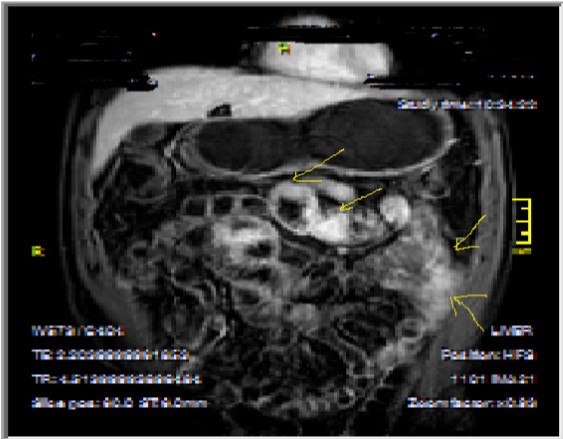

Bowel wall thickening with increased luminal and extra-luminal signal changes on FS images, showing active inflammation, edema in the adjacent intraperitoneal and mesenteric spaces, active inflammation; bowel wall thickening and enhancement on post-contrast T1W images plus high signal intensity on T2W- FS images7, 9, 12, 14, 17, 18, 19, 20, 21 (Figure 4a-b).

Chronic disease without active inflammation; Bowel wall thickening and enhancement on postgadolinium T1W images plus low signal intensity on T2W-FS images with possible stenosis and obstruction due to fibrosis, chronic disease with active inflammatoryexacerbations;these conditions can overlap with active inflammation, require longitudinal repeated scanning7, 12, 14, 20,26, 27, 28, 29, 30 (Figure 5a-b, Figure 6a-b)

Figure 4a.Mucosal involvement and lack of opacified ileal segments with loss of intestinal folds and increased bowel wall thickness due to Crohn’s disease on T2W coronal sequence after OCA, presented at 37 years old male with moderate Crohn’s disease.

Figure 4b.Mucosal, luminal and bowel wall involvement in Crohn’s disease with skipped lesions, seen at T2W axial image after OCA, presented at 45 years old male with severe inflammatory disease.